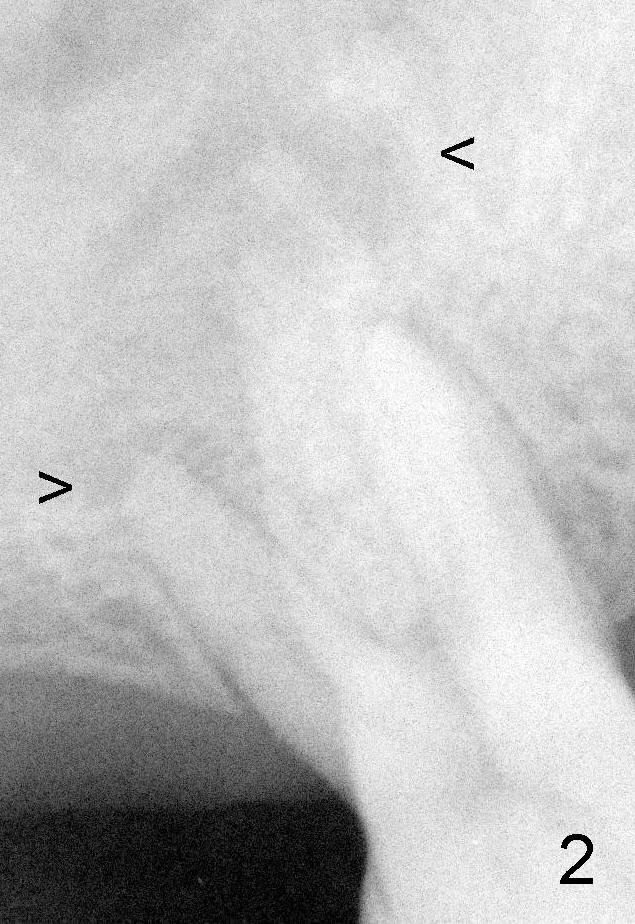

50岁男士有严重牙周炎(图一(2009年拍摄):二号牙(左上七)最终拔除(与图二对比)),最近三号牙(左上六)冷热痛,而且不能咬东西,三号牙多处牙周袋深,根尖片显示远中颊侧和腭侧根尖阴影(图二箭头),初步诊断:牙周牙髓综合症,需要根管治疗以及牙周手术,还可能保留不了。开髓表明活髓,近中颊侧和远中颊侧(DB)根管口很接近(参考图一图二),扩大(30/.04)后并表现不出来(图五至图七),开始近中根管口好像比较接近腭侧根管口,以为是MB2,使用Piezo超声波/diamond tip在MB(图六*)颊侧和近中寻找另外一个根管(箭头),但不成功。腭侧根管扩大到40/.06,匆匆忙忙插入主牙胶尖,拍摄根尖片(图三),显示远中颊侧以及腭侧(P)牙胶尖在相应牙根正中,但是近中颊侧并不是这样(图四=图三+MB牙根和牙胶尖轮廓),这说明还存在另外一个根管。经过再次合适扩大(crown down),腭侧牙胶尖进入更深地方(临床上),这时病人已经坐立不安了,paper points吸干根管后,拍摄图五至图七,暂封。由于病人还缺失好几颗牙齿,劝他去拍摄CT。今天术后第五六天,打电话给他,他很高兴,说冷热痛消失,牙齿也牢靠多了,但是还没去拍摄CT。下周三他回来完成根管治疗。

如果他还没有CT,我该怎么在没有外科显微镜下找遗留根管呢?MB和P根管口之间的确有一个沟(map),但是非常光滑(图五至图七),能找到根管口?还是往原来MB根管口颊侧探索?图三/图四暗示MB1还没有被发掘,对吗?MB2存在吗?